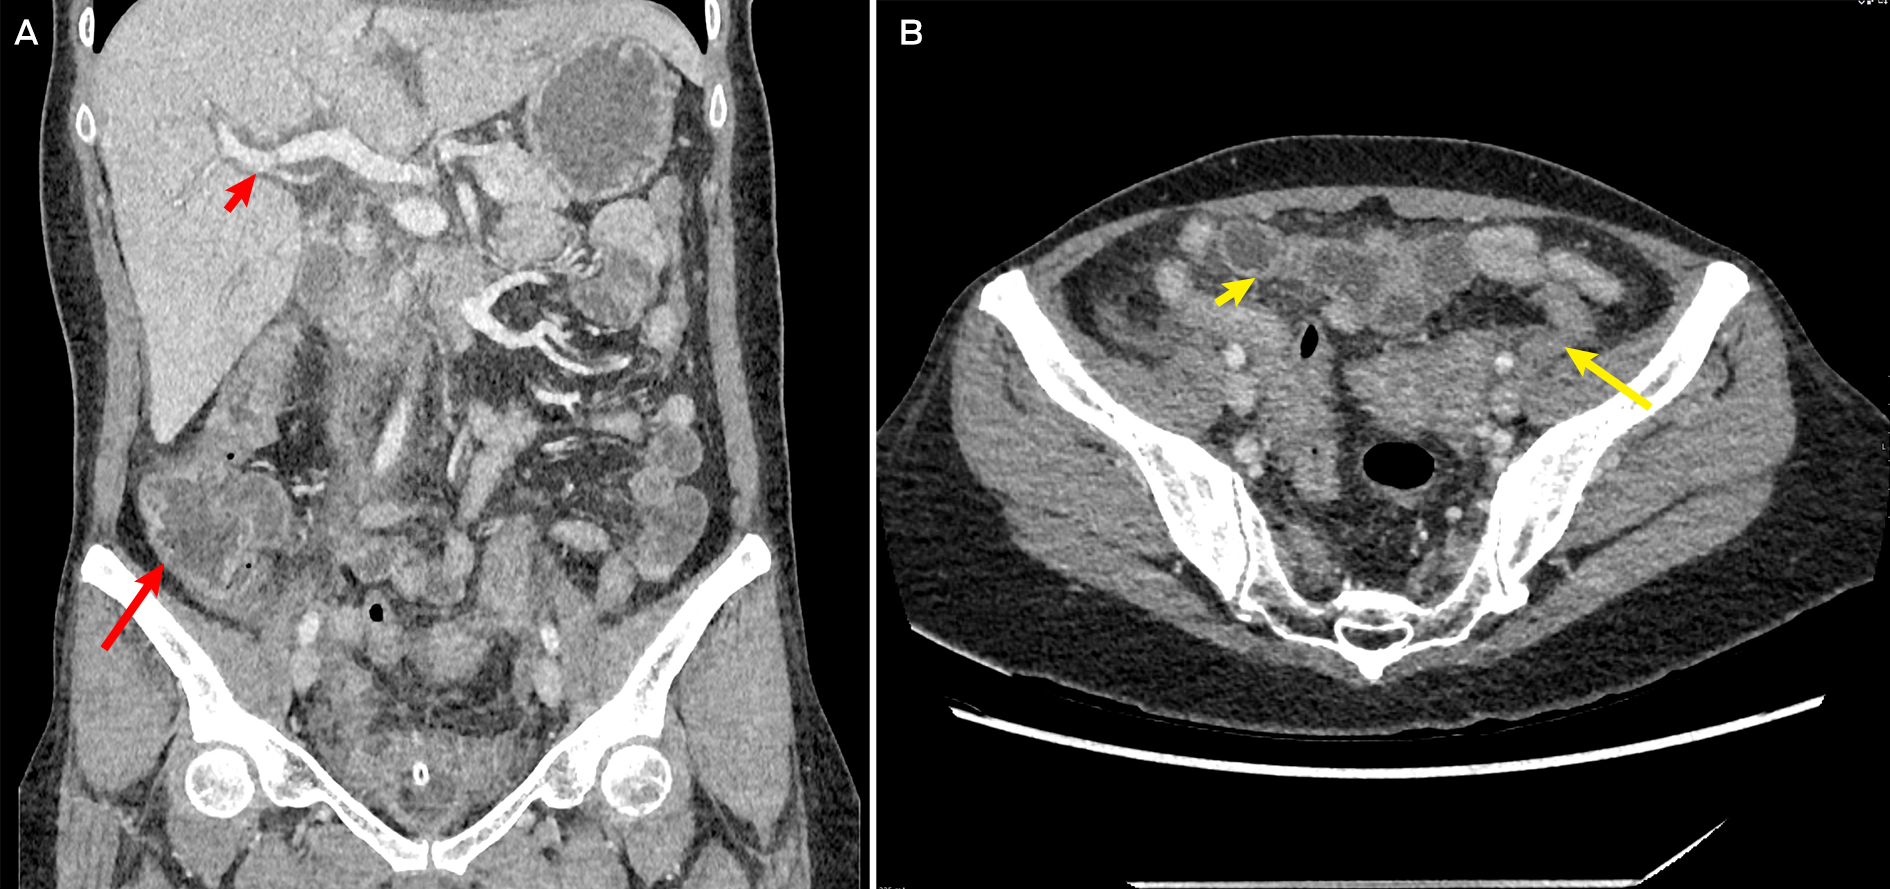

Initial investigations revealed an acute kidney injury (serum creatinine, 261 μmol/L; reference interval [RI], 45–90 μmol/L; baseline unknown but reportedly normal); mild transaminitis (alanine transaminase, 67 U/L [RI, 10–35U/L]; aspartate aminotransferase, 51 U/L [RI, 10–35 U/L]); neutrophilic leucocytosis (neutrophil count, 16.9 × 109/L [RI, 2–7 × 109/L]); and an elevated C‐reactive protein level of 423.4 mg/L (RI, ≤ 4.9 mg/L). The patient's lactate level was normal (1.9 mmol/L [RI ≤ 1.9mmol/L]). Computed tomography (abdomen and pelvis) showed severe pancolitis, with diffuse mural thickening from the ascending colon to the rectum, and trace free fluid in the pelvis (Box).

Box – Computed tomography of the abdomen showing pancolitis

A: Representative coronal slice showing prominent caecal and ascending colon mural thickening (long arrow) and periportal thickening (short arrow), suggestive of pancolitis. B: Axial slice showing prominent sigmoid (long arrow) and transverse colon (short arrow) mural thickening, consistent with overall diagnosis of pancolitis.